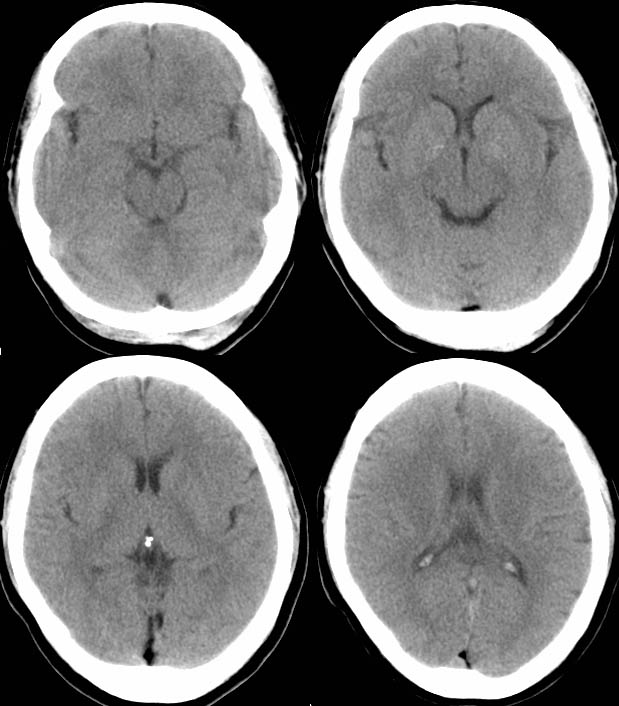

标题: CT7563:枕大池密度低

女,62,头昏

ct值是多少?如果是负值,那就是脂肪瘤。

皮样囊肿好发于后颅窝中线,可见特征性的皮瘘,ct值为负值,囊肿可因为反复感染而出现强化

脂肪瘤,主要在中线区,半数位于并柢体区,常有钙化,肿瘤无强化,无占位效应

畸胎瘤半数发生在松果体区,瘤内可出现特征性的骨骼,牙齿增强后实体部分有强化

本例病变在后颅窝中线,因为病灶内密度比较均匀,所以没有占位效应,左枕部皮下软组织比较厚,不知临床上有无皮瘘的表现,如果有就更能肯定诊断了

看图片ct值应该是负的,不过也不能由此断定就是脂肪瘤,皮样囊肿也可为负值